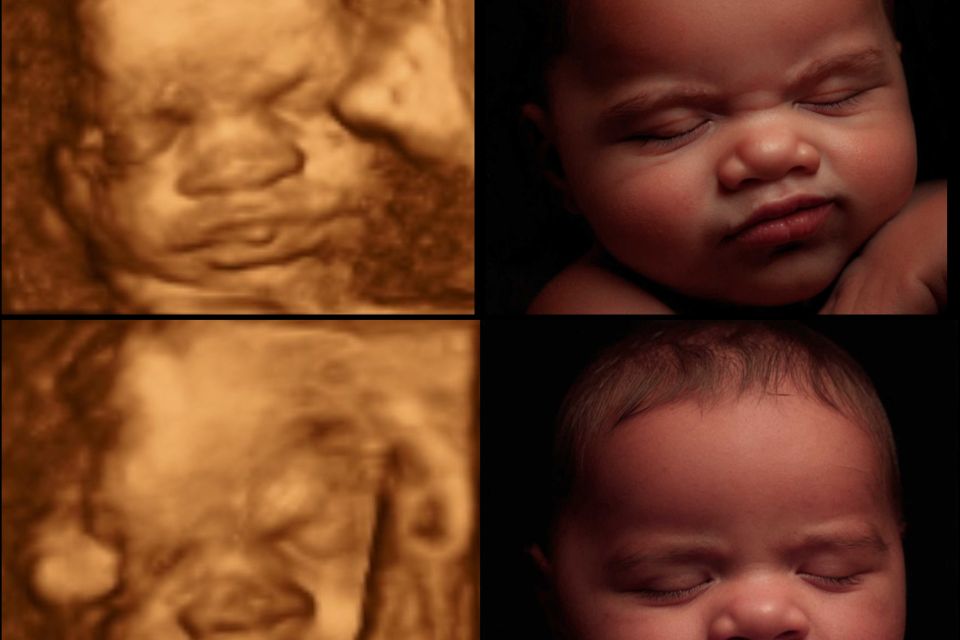

Most Realistic & lifelike photo you can get until the arrival of your little one. Using the newest technology to change your 3d/4d photo into something more realistic without changing any of your baby's features.